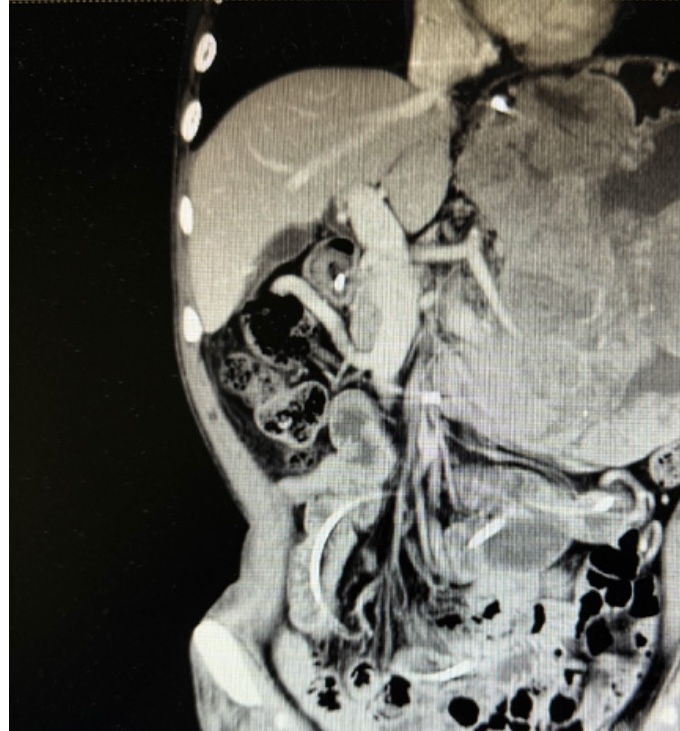

张翼主任医师接诊后,第一时间牵头对患者进行全面评估,经影像检查进一步确认:肿瘤体积巨大且与脾动脉粘连紧密,术中稍有不慎就可能引发致命性大出血,手术难度远超常规胃肠肿瘤手术。为最大程度降低风险,张翼教授先后多次组织全院大会诊,联合麻醉科、输血科、重症医学科、影像医学科等多学科专家反复推演手术方案,从手术入路的选择、血管保护的细节,到术中输血预案、术后并发症防控,每一个环节都制定了详尽的应对策略。

患者术前影像资料

经过严格的术前准备和周密的计划,在胃肠外科李小荣主任医师、肝胆胰外科余枭主任医师的指导下,由胃肠外科张翼主任医师、郭一航副主任医师团队联合肝胆胰外孙吉春副主任医师的多学科团队,成功为患者实施了腹腔巨大肿瘤及多脏器联合切除手术。术中,当团队切开腹腔后,巨大肿瘤与脾动脉的粘连程度远超术前预判,解剖结构模糊不清;随着分离操作的推进,患者在术中出血量逐渐增加,甚至高达 2000ml。面对紧急情况,张翼主任医师团队始终沉着冷静,凭借数十年积累的外科经验与精准的操作技巧,小心翼翼地剥离肿瘤与血管的粘连组织,避开每一处关键神经与分支血管,一步步 “拆解” 肿瘤对脾动脉的包裹。经过数小时的高强度手术,团队最终将完整的巨大肿瘤完整切除,手术顺利结束。